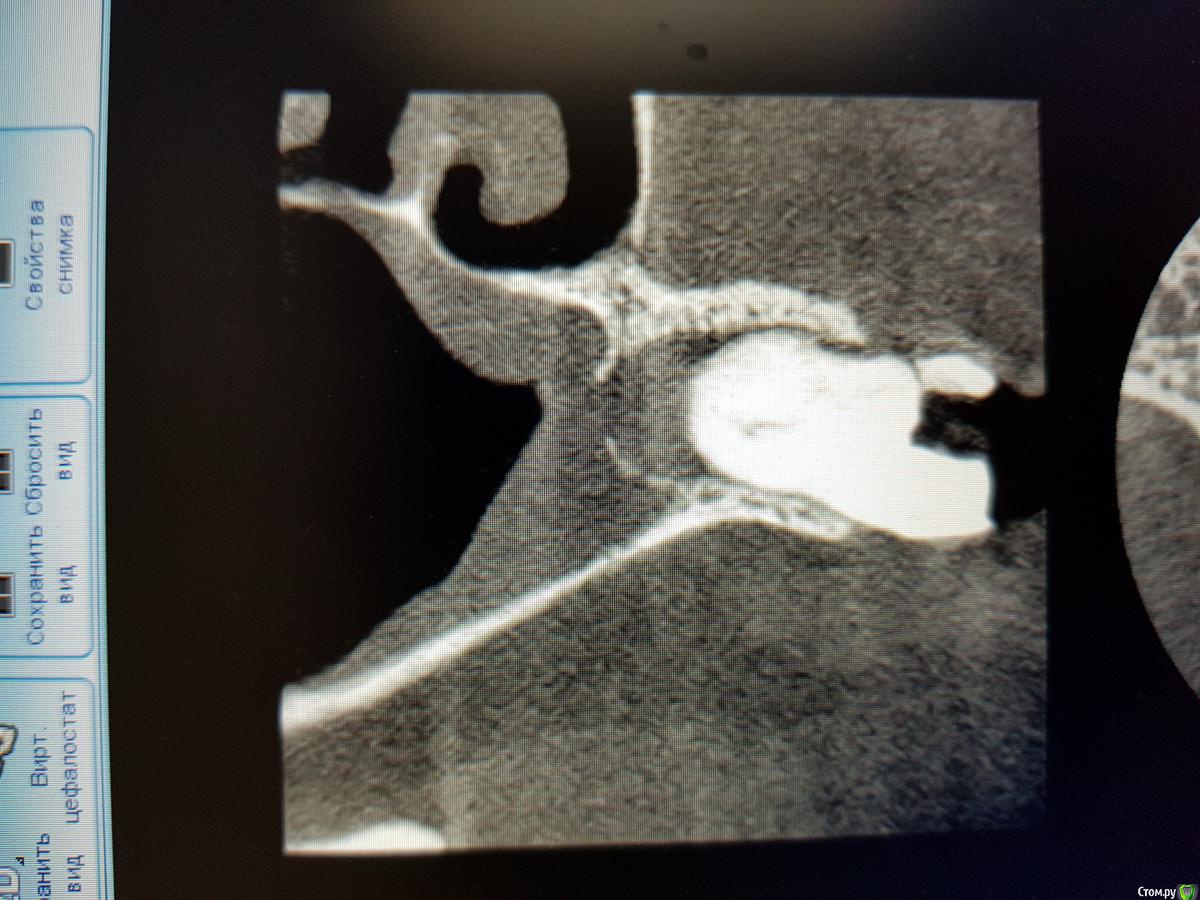

Kazankov.Egor Опубликовано 25 сентября, 2018 Поделиться Опубликовано 25 сентября, 2018 Фото до и после. В чём ошибка? Лунка полностью эпителизировалась без особенностей. Фото не перевернуть (второй раз). Ссылка на комментарий

Kostoprav Опубликовано 25 сентября, 2018 Поделиться Опубликовано 25 сентября, 2018 не совсем понятно по рг, в лунке каша? Ссылка на комментарий

Kazankov.Egor Опубликовано 25 сентября, 2018 Автор Поделиться Опубликовано 25 сентября, 2018 не совсем понятно по рг, в лунке каша?Не открывал...В прошлый раз при такой картине была плотная кость. Волнует слизистая пазухи. В остальных местах изменения пропали. Ссылка на комментарий

Kostoprav Опубликовано 26 сентября, 2018 Поделиться Опубликовано 26 сентября, 2018 я на такие изменения слизистой не обращаю внимания. главное что бы соустие не было заблокировано . 5 Ссылка на комментарий

Nazim_NV86 Опубликовано 27 сентября, 2018 Поделиться Опубликовано 27 сентября, 2018 27? Измерение толщины кости до дна ? Синус будет или нет ? Если да, то открытый нинзя и как минимум откачать её, как максимум после отслойки вылущить через прорезь мембраны. 1 Ссылка на комментарий

Bier Опубликовано 29 сентября, 2018 Поделиться Опубликовано 29 сентября, 2018 27? Измерение толщины кости до дна ? Синус будет или нет ? Если да, то открытый нинзя и как минимум откачать её, как максимум после отслойки вылущить через прорезь мембраны.можно ничего не делать, просто поднять. 4 Ссылка на комментарий